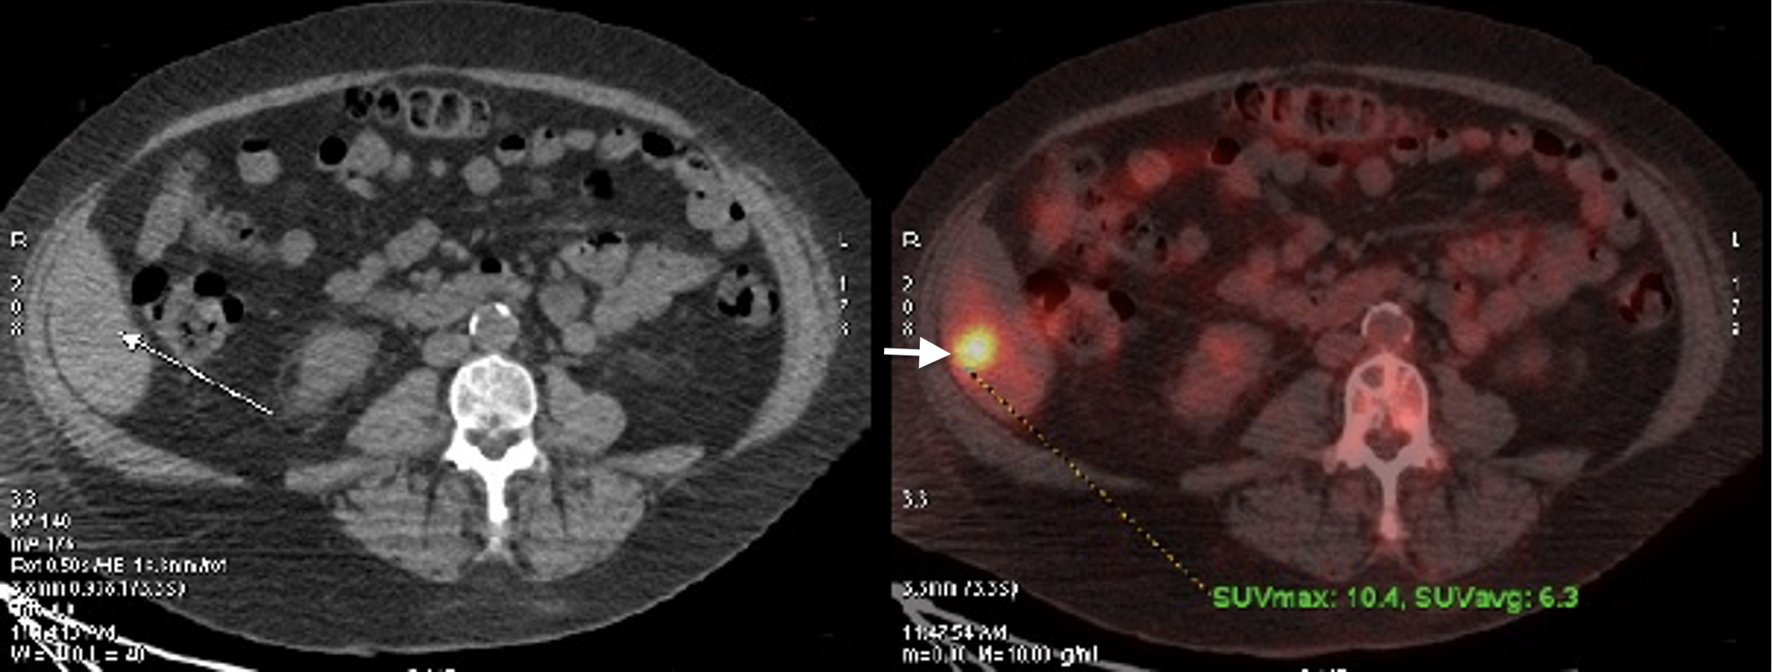

PET scan was repeated in January 2018 and showed interval development of several new FDG avid osseous lesions in the axial and appendicular skeleton as well as an incidentally detected intense hypodense lesion inferiorly in the posterior aspect of the right hepatic lobe with another small, but FDG avid focus more superiorly and medially in the posterior aspect of the right hepatic lobe. She was subsequently referred to an academic hospital by her primary oncologist due to progression of disease on PET (Figs. 1-3). Percutaneous biopsy of this newly identified liver lesion was performed from hepatic segment 6 and the pathology showed numerous abnormal plasmacytoid cells consistent with MM (Figs. 4 and 5). Interestingly, the patient did not have any symptoms or evidence of hepatomegaly on examination. Her liver function tests remained normal at the time of detection of the liver plasmacytoma and for the remainder of her disease course.

![]() Click for large image | Figure 3. Positron emission tomography scan at the time of relapse showing liver involvement. |